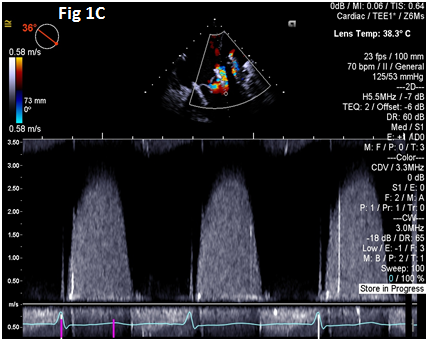

A 73-year-old female with mechanical mitral valve, tricuspid annuloplasty (32mm Edwards Physio Tricuspid incomplete ring) underwent Transcatheter Tricuspid Valve Replacement (TTVR) using off-label 29mm Edwards Sapien 3 (S3) Transcatheter Heart Valve (THV). Immediate post valve deployment, mild Perivalvular Leak (PVL) was noticed at the septal aspect (area of incomplete annuloplasty ring). Eighteen months later, patient presented with recurrent right heart failure and paracentesis due to severe tricuspid PVL (Figure 1A-C, Video 1). Percutaneous PVL closure under general anesthesia, Trans-esophageal Echocardiography (TEE) was performed. Via femoral venous access, defect was easily crossed with Agilis steerable sheath, multipurpose catheter and 0.035” glide wire. Despite recurrent attempts, wire came through the PVL but then traversed through open cells of S3 into the right ventricle (Figure 2A), confirmed with Armada 6mm balloon waist at the S3 cage (Figure 2B) (despite inflating 28mm Z med balloon inside S3 cage, Figure 2C). We decided to partially deploy the plug and assess valve function. Using 7.5F Asahi Eaucath multipurpose guide, a 12mm AmplatzerTM Vascular plug II (AVP II) was advanced through the defect. The ventricular disc was opened inside the S3 cage while body in the PVL defect (outside the S3 cage) and atrial disc on the atrial side of PVL (Figure 3A-B). With S3 function unaffected, no central leak and minimal gradient, PVL reduced to mild severity (Figure 4A-D, Video 2); the AVP II was successfully deployed (Figure 5). At 3-month follow up, there was an excellent symptomatic improvement (NYHA functional class I), with no heart failure re-hospitalization or paracentesis. Deployment of plug disc inside the valve frame is not recommended due to fear of interference with leaflet function and possible injury in long term. There was no immediate issue with the valve function in this case (due to space between the leaflet and frame of S3 and depends on size of plug used). Valve-in-Valve (S3-in-S3) would have certainly sealed all open cells treating this PVL but is more expensive option.

Figure 1 Para-valvular leak shown by color Doppler (1A) on 2D and 3D (1B) images, along with dense tricuspid spectral Doppler signal with peak velocity of 3m/s (1C).